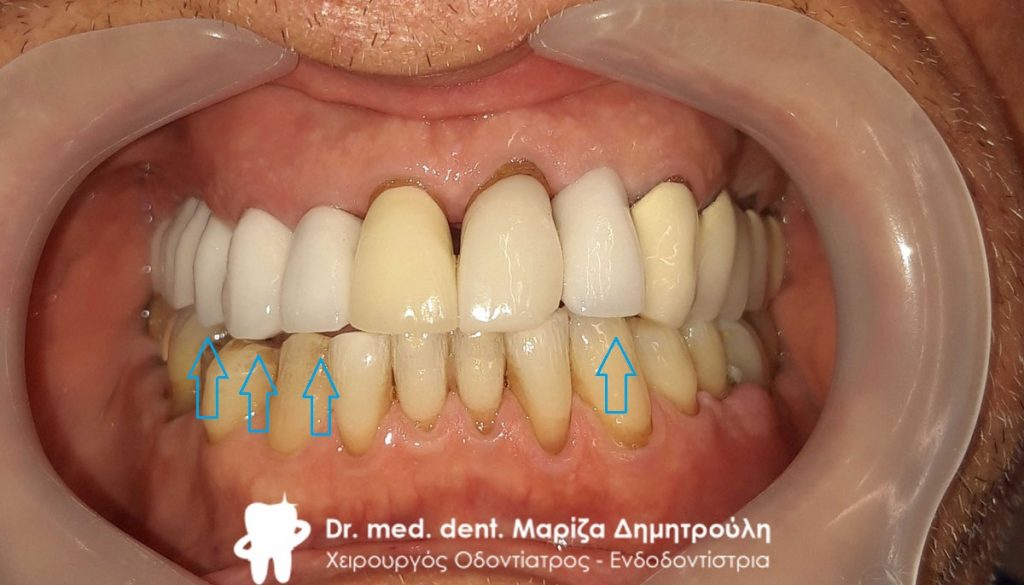

Ο ασθενής επισκέφτηκε το ιατρείο με σκοπό την αποκατάσταση του μεγάλου ελλείμματος στη δεξιά πλευρά της άνω γνάθου όπως επίσης και την αντικατάσταση μιας παλιάς θήκης στη δεξιά πλευρά της άνω γνάθου. Όπως δείχνουν και οι φωτογραφίες πραγματοποιήθηκε και αντικατάσταση παλιών λευκών σφραγισμάτων στη δεξιά πλευρά της κάτω γνάθου.

Τελική εικόνα